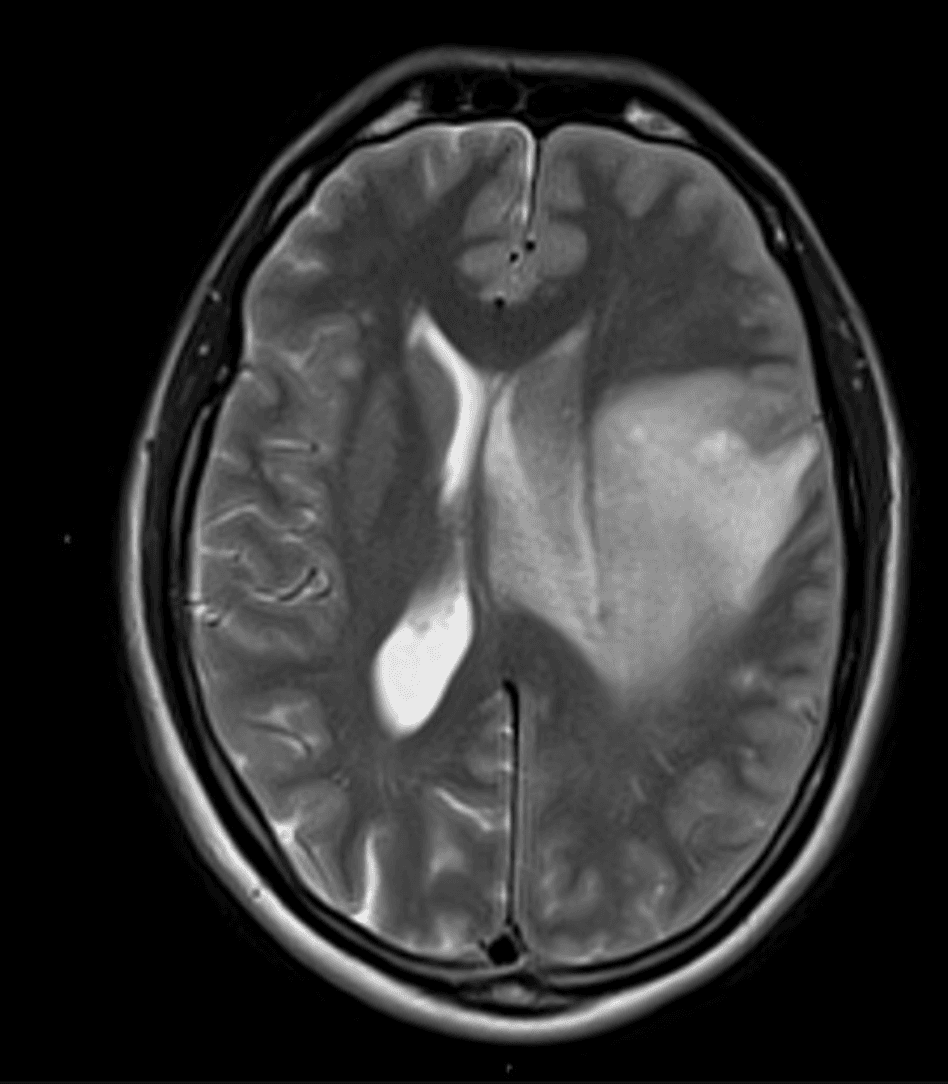

Laboratory studies show white blood cell count 4.8 x 10^3/uL, hemoglobin 11.2 g/dL, platelet count 211 x 10^3/uL, and creatinine 0.9 mg/dL. Serum cryptococcal antigen remains positive at a low unchanged titer. Lumbar puncture reveals opening pressure 18 cm H2O, 4 white blood cells/uL, protein 61 mg/dL, glucose 58 mg/dL, negative fungal culture, and negative CSF cryptococcal antigen by lateral flow assay. CSF toxoplasma PCR is negative, Epstein-Barr virus DNA is not detected, and JC virus PCR is positive at low level. Brain MRI demonstrates a large asymmetric left frontal subcortical T2 hyperintense lesion.

Axial T2-weighted brain MRI demonstrates an expansile left frontal white matter lesion with mass effect, leftward midline shift, and subfalcine herniation.